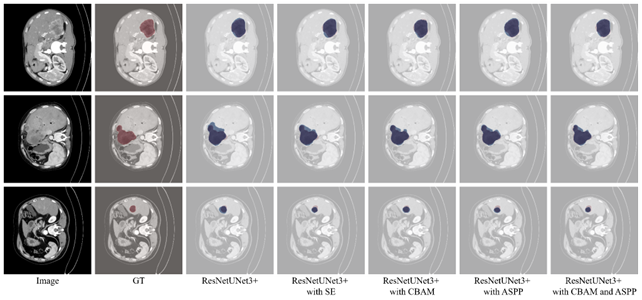

Refer to caption

Figure 7: The visual comparison of segmentation results of ResNetUNet3+ and its variants against ground truth on the testing set. The predicted and GT are highlighted in blue and red, respectively.

Figure 7 shows a qualitative comparison of segmentation results from the baseline model and its variants, including attention modules (SE, CBAM) and a multi-scale feature extractor (ASPP), against the ground truth on three test images. The baseline model generally identifies lesions well but sometimes produces imprecise boundaries. The CBAM variant offers improved segmentation accuracy, especially in capturing irregular lesion contours, as seen in the second row. This indicates that CBAM’s spatial and channel-wise attention enhances the model’s ability to differentiate lesions from healthy tissue, resulting in more precise masks.